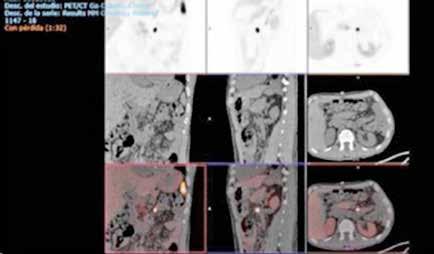

Tres meses después se realiza un nuevo TC de control, que muestra la lesión en el mismo lugar, actualmente de 7,4x5,9 cm de diámetros (previo de 9,8x7,5 cm). En la actualidad se ha alejado de las VSH, pero contacta y desplaza la vena porta derecha y la arteria hepática. Además se visualiza una leve dilatación de la vía biliar intrahepática izquierda, de nueva aparición. Se presenta en comité una vez más y se decide colocar un drenaje biliar interno-externo, dado la dilatación de vía biliar que presenta el paciente. Además se realiza una embolización portal derecha, para así aumentar el remanente del hígado izquierdo que era del 29%. Se realiza una nueva volumetría hepática tras la embolización portal y se comprueba que el futuro remanente hepático había aumentado al 42%.

Resumiendo: Teníamos una masa hepática inicialmente irresecable que se ha tratado con dos embolizaciones arteriales, consiguiendo una disminución del tamaño y una mayor separación de las venas suprahepáticas. Sin embargo, se ha acercado a la bifurcación portal y comprime la vía biliar (dilata la vía intrahepática izquierda asociando una elevación de bilirrubina). Se ha colocado un drenaje biliar interno-externo. Se ha embolizado la porta derecha, consiguiendo pasar de un volumen de remante hepático del 29% al 42%, siendo ahora posible su resección. El acceso a las VSH sigue siendo complejo y arriesgado, pero menos que al inicio (Figura 4).

Figura 4.

TC realizado tras las dos embolizaciones arteriales. Vemos cómo la lesión ha disminuido considerablemente de tamaño y ahora está más alejada de las VSH y de la cava. Esto permite la ligadura de las VSH en su confluencia con la cava. Inicialmente no habría sido posible por su cercanía y tamaño.